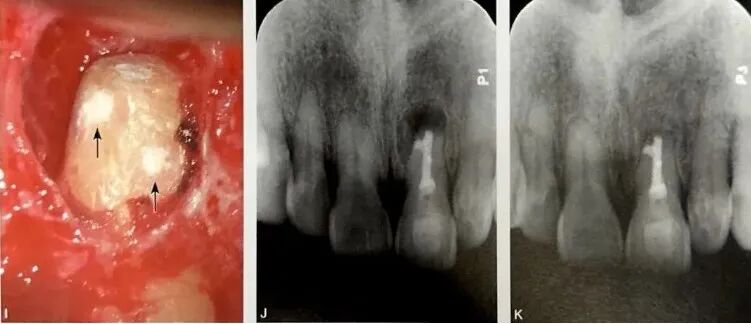

根管侧支的直径通常小于100 mm,因此术前影像学诊断比较困难。当侧支比较粗大时,有可能在CBCT上清晰呈现,如图4所示,A为口内像颊侧面观,示左上颌中切牙根尖周窦道;B为根尖片,示根管充填良好,根尖周透射影;C为CBCT状位;D为CBCT冠状位,示根管侧支(箭头示);E为CBCT水平位,示根管侧支(箭头示);F为根尖周刮治后染色探查,见根管侧支2处(箭头示);G为根尖切除后染色探查见根管侧支3处(箭头示,左上角2处箭头为显微口镜镜像拍摄);H为根管和侧支逆行预备(近中近根尖段2处侧支融合);I为根管和侧支逆行充填(箭头示);J为术后根尖片;K为术后26个月随访根尖片,示根尖周完全愈合。